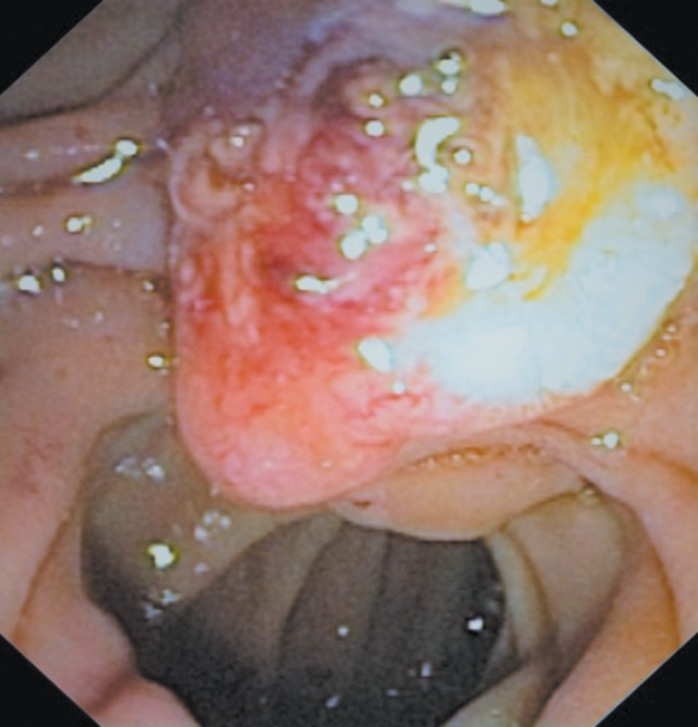

The patient was additionally examined. An ultrasound examination of the abdomen revealed moderate hepatosplenomegaly, signs of chronic pancreatitis, and secondary renal changes. According to fibrogastroduodenoscopy (Fig. 1), a giant major duodenal papilla (MDP) with an altered structure (25 mm in diameter, up to 50 mm in length), with a cyanotic surface, and areas of necrosis over the entire surface were visible in the postbulbar region of the intestine. There was hemorrhage from multiple sections of the altered MDP.

Fig. 1. Endoscopic view of the Vater’s papilla tumor after initiation of treatment with proton pump inhibitors

Рис. 1. Эндоскопическая картина после начала терапии блокаторами протонной помпы. Изъязвленная опухоль большого дуоденального сосочка с признаками состоявшегося кровотечения